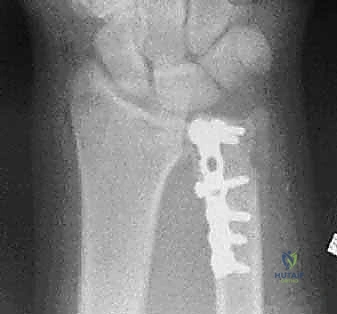

استخدام الأشعة السينية في التشخيص

بروتوكول التصوير الطبي المتقدم

لا يكتفي الدكتور هطيف بالفحص السريري، بل يعتمد على أحدث تقنيات التصوير لضمان "الأمانة الطبية" في التشخيص:

1. الأشعة السينية (X-rays): بوضعيات متعددة (أمامية خلفية، وجانبية دقيقة). الوضعية الجانبية الحقيقية (True Lateral) حاسمة لاكتشاف أي خلع جزئي في المفصل (DRUJ).

2. الأشعة المقطعية ثلاثية الأبعاد (3D CT Scan): تُستخدم في الكسور المفتتة أو كسور رأس الزند المفصلية المعقدة، حيث تعطي خريطة دقيقة للجراح قبل الدخول لغرفة العمليات.

ثانياً: العلاج الجراحي (Surgical Intervention)

متى يقرر الدكتور هطيف ضرورة التدخل الجراحي؟

1. عدم الاستقرار (Instability): إذا كان المفصل الزندي الكعبري البعيد (DRUJ) غير مستقر بعد تثبيت كسر الكعبرة.

2. الانزياح (Displacement): إذا كان الكسر في قاعدة الناتئ الإبري منزاحًا بأكثر من 2 ملم.

3. الكسور المفصلية: أي كسر يخل بتطابق السطح المفصلي لرأس الزند.